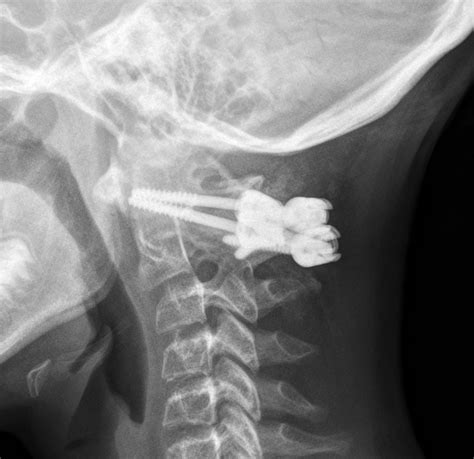

• Imaging studies: X-rays, MRI, or ultrasound to visualize the affected joints and entheses. MRI is particularly useful for detecting inflammation in the sacroiliac joints.